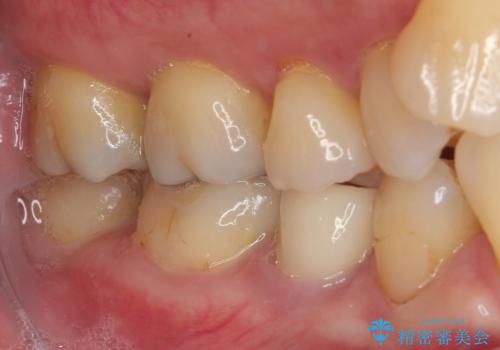

特に異常もなく見た目、噛み合わせともに満足していただけました。

ラバーダム防湿を行い、セラミックの接着をすることで、唾液や血液などの接着阻害因子を排除することができます。

歯と歯の間の虫歯をコンポジットレジンで治すと段差ができたりして清掃性が悪くなるので、セラミックインレー修復やゴールドインレー修復などの適合の良い詰め物で治療することをオススメします。